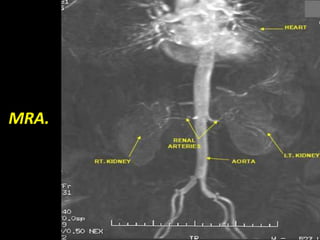

MR Angiography.

Right pelvic renal transplant

as seen on MRA.

MRA.

MR Angiography. Right pelvicrenal transplant as seen on MRA.